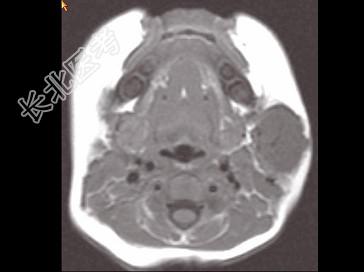

- 单项选择题男,40岁, 左面部渐进性增大的包块,MRI检查如图所示, 最可能的诊断是 ( )

A、左面部毛细血管瘤

B、左面部囊肿

C、左面部脓肿

D、左面部脂肪瘤

E、左面部神经纤维瘤